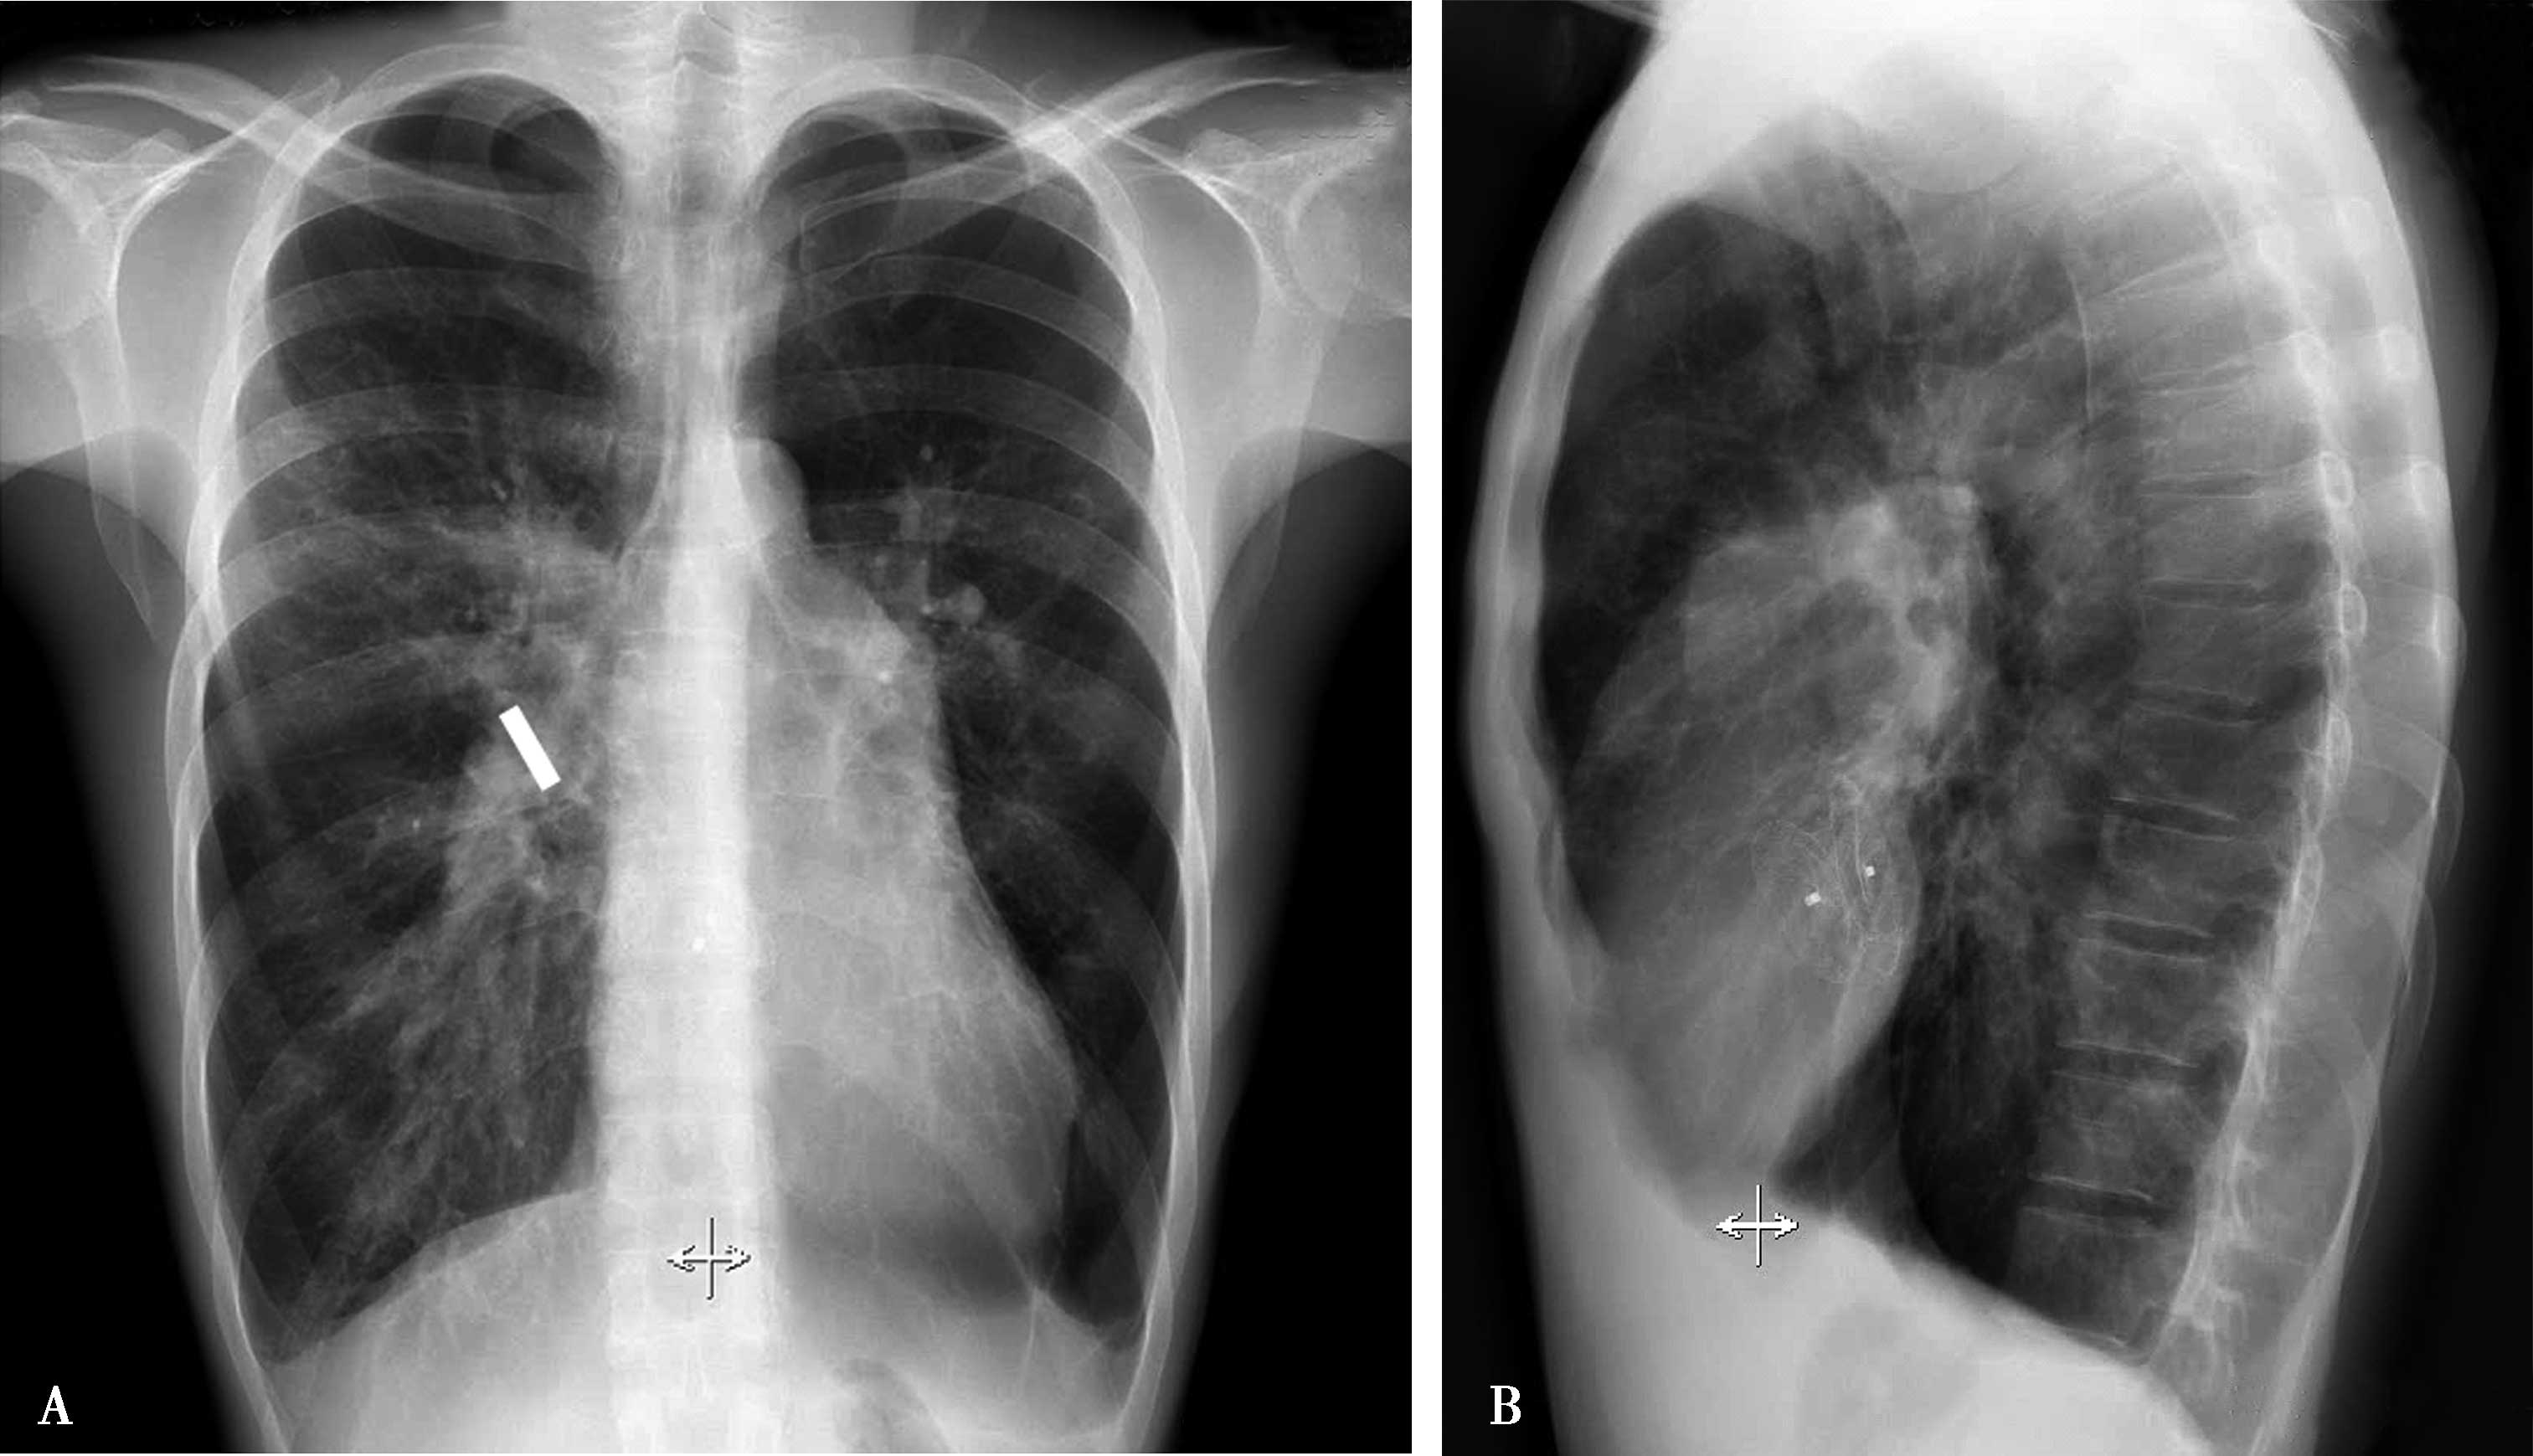

(三)慢性血栓栓塞性肺动脉高压

慢性血栓栓塞性肺动脉高压(CTEPH):较大肺动脉由于慢性栓塞而闭塞,继发较小肺动脉内膜、中膜增厚,管腔狭窄-闭塞,原位血栓形成并发类似IPAH的丛样病变,加重肺动脉高压。

X线征象:①重度肺动脉高压;②中心肺动脉扩张,右下肺动脉增宽呈截断现象,外周分布不均,部分缺支、部分迂曲扩张;③肺内陈旧梗死灶;④右心高度增大(图7-2-11)。

图7-2-11 男,38岁,慢性肺栓塞5年,超声测肺动脉压110mmHg。A.胸部正位两肺纹理分布不均,两下肺纹理稀少,右下肺动脉增宽呈截断现象,上肺动脉迂曲增宽;肺动脉段高度凸出(↑),右心房室增大;B.左侧位心前间隙缩小,肺动脉圆锥扩张(↑)。X线胸片诊断:慢性血栓栓塞性肺动脉高压

(四)二尖瓣狭窄肺动脉高压

二尖瓣狭的血流动力学改变是左心房-肺静脉压持续升高(左心房平均压10mmHg以上),出现肺静脉高压,随着肺静脉高压的发展,逐渐导致肺泡-毛细血管膜发生不可逆性重构,肺的弥散功能降低;肺小动脉肌化、中膜增厚、远端肺动脉新生内膜生成,导致肺血管阻力(PVR)增加,发生毛细血管后肺动脉高压,并逐步加重。

X线征象:肺淤血,左心房及右心室增大,肺循环高压(肺动脉高压+肺静脉高压)(图7-2-12)。

图7-2-12 男,36岁,二尖瓣狭窄,肺动脉高压。X线片,AB.两肺间质性肺水肿,肺动脉高压(右下肺动脉2.0mm↑),左心房、右心室增大(↑),诊断二尖瓣狭窄,肺循环高压(肺动脉及肺静脉高压);C.超声心动图:二尖瓣口面积:1.02cm 2 (↑);PAP:78mmHg